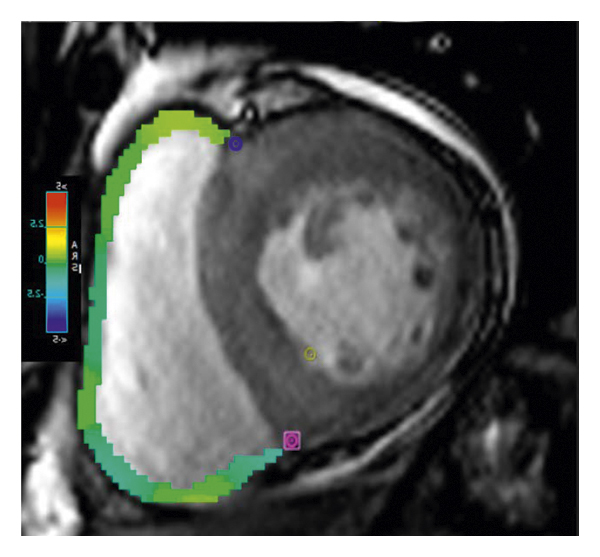

2.3. 이미징 분석모든 이미지 분석은 시중에서 판매되는 소프트웨어(cvi42, Circle Cardiovasic Imaging, Inc. Calgary, Canada)를 사용하여 수행되었습니다. 심장 기능을 측정하기 위해 심장내막 및 심외막 추적을 확장기 말기 및 수축기 말기의 직렬 단축 슬라이스에서 수동으로 수행했습니다. LV/RV 확장기말 용량(EDV), 수축기말 용량(ESV) 및 LV/RV 박출률을 포함한 전체 LV/RV 수축기 기능이 계산되었습니다. LV 및 RV 심근 스트레인 분석은 장축 4챔버 및 단축 슬라이스를 조직 추적 모듈에 로드하여 수행되었습니다(그림 1 (a) 및 1 (b)). RVT는 중실의 3회 측정하였고, 평균 두께를 계산하였다(도 1 (c) 및 1 (d)). GRPS(글로벌 라디칼 피크 변형), GLPS(글로벌 세로 피크 변형) 및 GCPS(글로벌 원주 피크 얼룩)를 포함하여 전역 특징 추적 매개변수가 자동으로 획득되었습니다. 최고 수축기 변형률(PSSR, 이완기부터 다음 수축기까지의 모든 단계에 대한 절대값의 최대 변형률)과 최고 확장기 변형률(PDSR, 수축기부터 다음 수축기까지 모든 단계에 대한 절대값의 최대 변형률)은 다음과 같습니다. 또한 분석했다. 양수 기호와 음수 기호는 서로 다른 동작 방향을 나타냅니다. 앞서 기술한 바와 같이[ 16 ], 정상적인 RVT 값은 7mm 이하로 정의되었다. 기준에 따라 CA 및 HCM 환자를 RV 비대(RVT >7 mm) 또는 RV 비대(RVT ≥7 mm) 환자에 따라 하위 그룹으로 나누었습니다.

(비) -